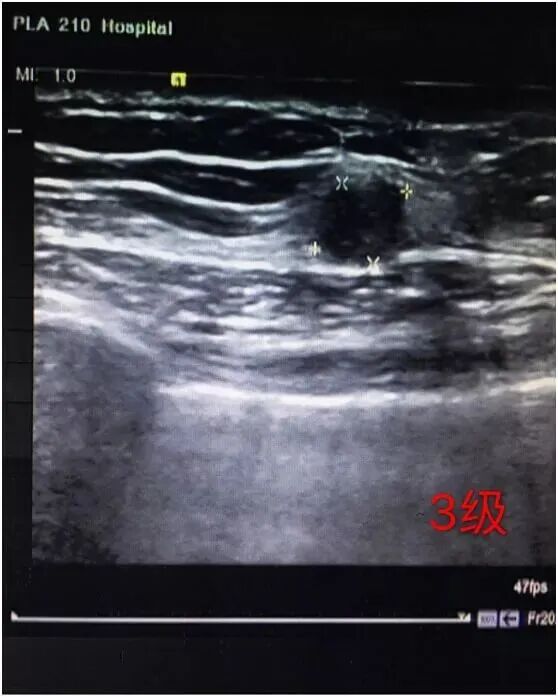

3级

良性病变的可能大,恶性率较2级更高,但小于2%。所以需要缩短复查随访周期(如3~6个月一次)。必须强调的是,此类并非是不确定的类型。例如:

(1)、年龄<40岁的纤维腺瘤或首次超声检查年龄<25岁的考虑纤维瘤可能性大。

(2)、实性椭圆形、边界清、纵横比<1的肿块,良性可能大,恶性的危险性<2%。

(3)、经过连续2至3年的复查可将原先的3级(可能良性)改为2级(良性)。

(4)、多发性复杂囊肿或簇状小囊肿。

(5)、瘤样增生结节(属不确定一类)。

(6)、术后建议短期随访(3-6个月)及其他检查。